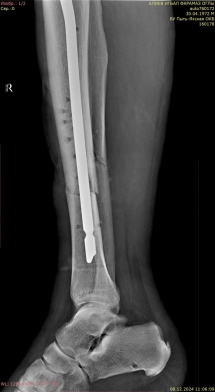

1) Мужчина, 35 лет. ДТП, водитель. Поступил в экстренном порядке. Диагноз — закрытый оскольчатый перелом дистального метаэпифиза правой большеберцовой кости, перелом наружной лодыжки правой голени со смещением отломков (рис. 1).

Рис. 1.